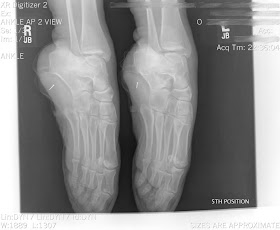

The picture above demonstrates this area of weakness, with a grade 3 Salter-Harris fracture.

The diagnosis and classification of a growth plate injury is normally via x-ray, and is classified as 1 to 5 Salter-Harris fracture.